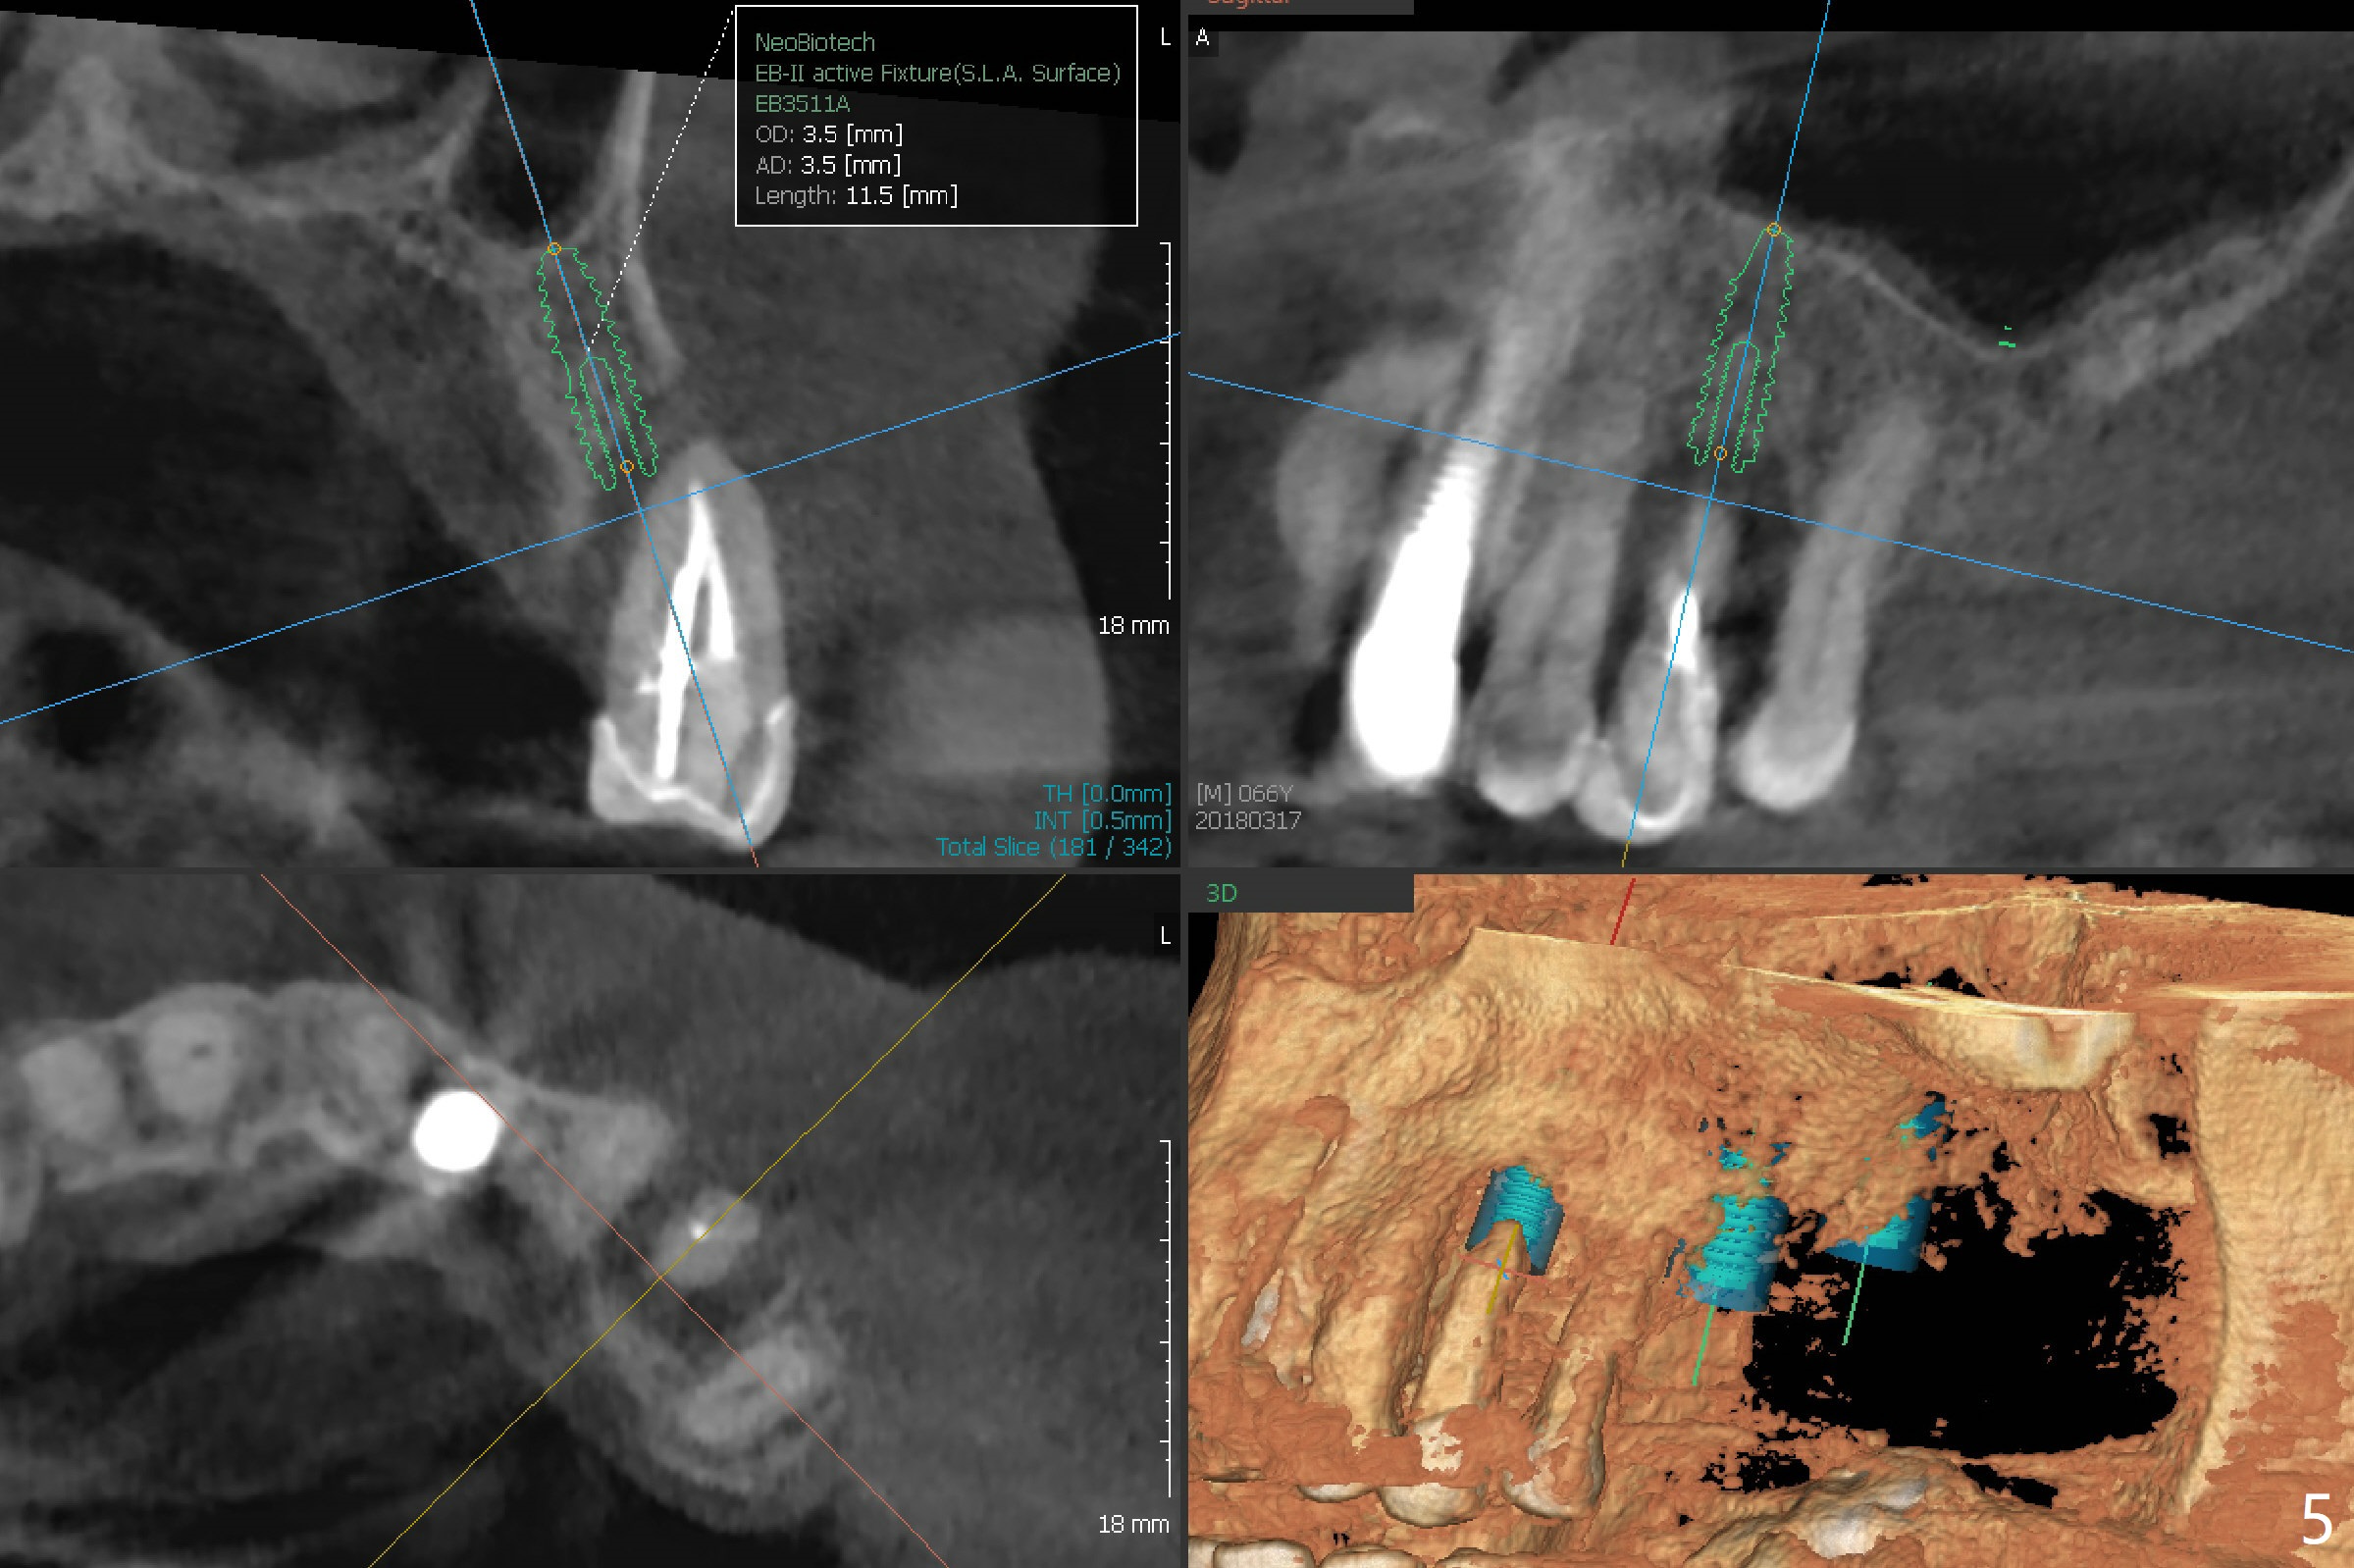

A 61-year-old man with chronic periodontitis presented to clinic for several implant placement (#3 10 14/15 18 30). For the tooth #12 (Fig.1), RCT was rendered (Fig.2). The tooth is non-salvageable 4.5 years post-treatment (Fig.3). Uneven bone loss mesiodistally makes implant placement challenging (Fig.4). A long implant will be used with ~3 mm subcrestal (mesially) and ~3 mm supracrestal (distally). A 3.5 or 4.0x13 mm implant will be placed subcrestal palatally and supracrestal buccally (Fig.5).